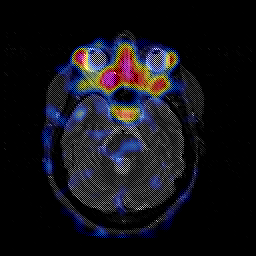

Glioblastoma multiforme overlay -- Slice #18

[Home][Help][Clinical][Tour 1][Tour 2][Tour 3] Slice 18